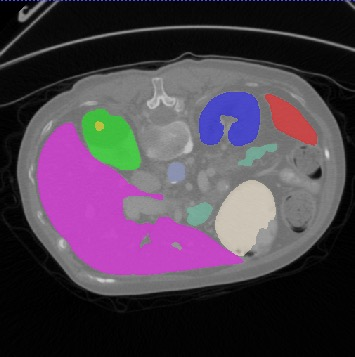

Transformers, the default model of choices in natural language processing, have drawn scant attention from the medical imaging community. Given the ability to exploit long-term dependencies, transformers are promising to help atypical convolutional neural networks (convnets) to overcome its inherent shortcomings of spatial inductive bias. However, most of recently proposed transformer-based segmentation approaches simply treated transformers as assisted modules to help encode global context into convolutional representations without investigating how to optimally combine self-attention (i.e., the core of transformers) with convolution. To address this issue, in this paper, we introduce nnFormer (i.e., Not-aNother transFormer), a powerful segmentation model with an interleaved architecture based on empirical combination of self-attention and convolution. In practice, nnFormer learns volumetric representations from 3D local volumes. Compared to the naive voxel-level self-attention implementation, such volume-based operations help to reduce the computational complexity by approximate 98% and 99.5% on Synapse and ACDC datasets, respectively. In comparison to prior-art network configurations, nnFormer achieves tremendous improvements over previous transformer-based methods on two commonly used datasets Synapse and ACDC. For instance, nnFormer outperforms Swin-UNet by over 7 percents on Synapse. Even when compared to nnUNet, currently the best performing fully-convolutional medical segmentation network, nnFormer still provides slightly better performance on Synapse and ACDC.